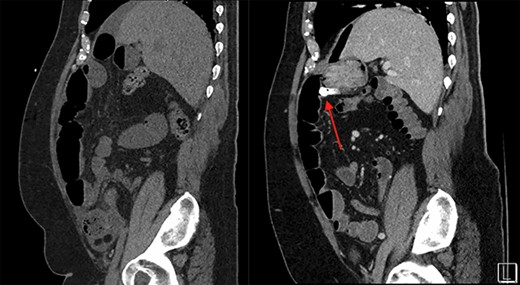

On the left is the initial CT scan non-contrast demonstrating dilated small bowel loops and a transition point in the right lower quadrant. On the right is the CT angiography (CTA), performed a week later, showing a mass and pill cam in the right upper quadrant.

The patient is a 69-year-old male with a past medical history of hypertension, chronic kidney disease, chronic obstructive pulmonary disease, right renal cancer status post-laparoscopic nephrectomy in 2016 (pathology showed renal cell carcinoma with invasion into the adrenal gland, Fuhrman nuclear grade 3–4, pT4 pN0, Stage IV) who presented to the emergency room (ER) with abdominal pain. The patient recently underwent an esophagogastroduodenoscopy and a colonoscopy the week prior as a workup for anemia, which were unremarkable. Since then, he started having intermittent abdominal pain and bloating. The CT abdomen and pelvis without contrast in the ER showed multiple dilated small bowel loops with a transition point in the right lower quadrant (Figs 1 and 2). Due to his history of previous abdominal surgery, this was diagnosed as a small bowel obstruction secondary to adhesions. He was initially managed with a nasogastric tube and gastrografin study. On hospital Day 1, he had minimal output from his nasogastric tube and started to have bowel movements; therefore, his nasogastric tube was removed and he was started on a liquid diet. His diet was advanced, and on hospital Day 2, the patient was discharged.

The next week, unbeknownst to his Gastroenterologist about his recent small bowel obstruction admission, he then proceeded with a capsule endoscopy study to assess for other causes of his anemia. He tolerated the pre-operative bowel preparation without issues. After swallowing the capsule, he subsequently had bloody bowel movements. He then went to the ER and found to have a hemoglobin of 7.1, which was decreased from his prior week’s hospitalization, 8.4. A CT angiography (CTA) abdomen and pelvis was then performed that showed a 4 × 6 × 4.1 cm mass in the right upper quadrant with the capsule endoscopy at the level of the mass (Figs 1 and 2). The images from the capsule were unremarkable. On review of his imaging with radiology, it appeared that this mass was not apparent without IV contrast on his previous CT scan a week prior. In addition, a prior CT abdomen pelvis with IV contrast 10 months ago was negative for a small bowel mass. A repeat abdominal and pelvis CT with oral and IV contrast was done for confirmation. This re-demonstrated the 6 cm mass with the capsule stuck proximal to it; therefore, we performed a diagnostic laparoscopy.